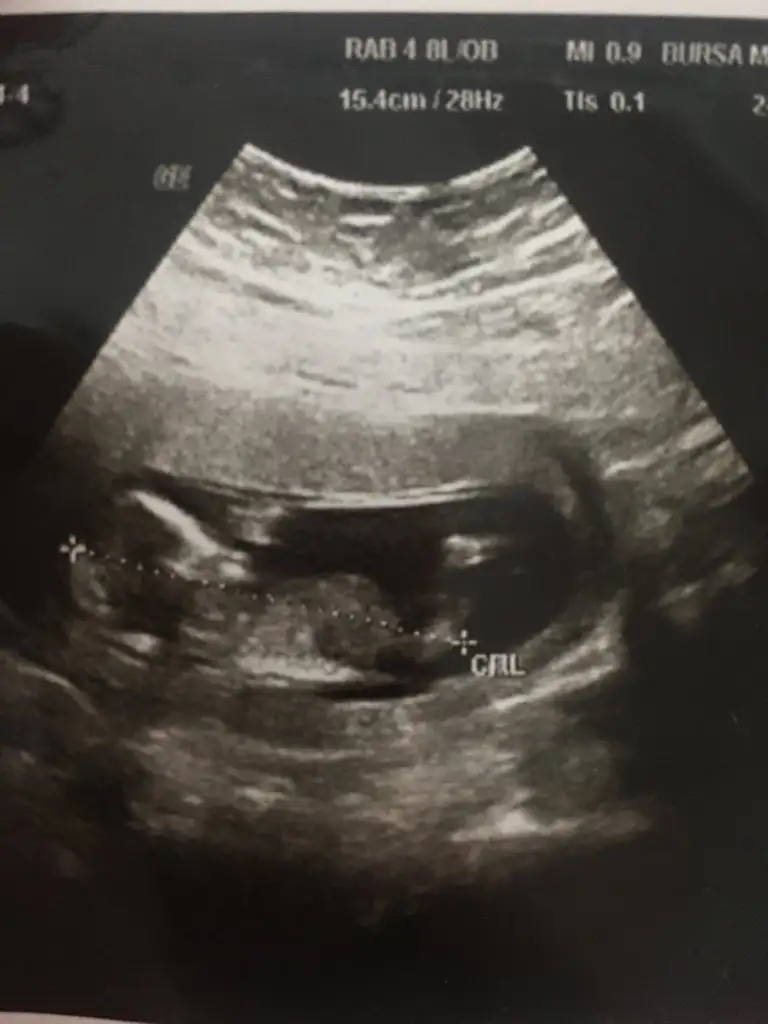

bu bir erkek bebek genital nub cikintisi gayet yukarda